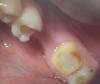

Bobby Опубликовано 10 июля, 2012 Поделиться Опубликовано 10 июля, 2012 Я так понимаю речь про мостовидный протез, одна опора - полная коронка, а вторая вкладка. Верно? А что тут оценивать? Ссылка на комментарий

Prosthodontist Опубликовано 11 июля, 2012 Поделиться Опубликовано 11 июля, 2012 Если оценивать в плане планирования, то если будет мостовидный протез, не о какой функции речи здесь и речи не может быть. Для того чтоб оценить препарирование под вкладку, то фотография этого не предоставляет. 47 зуб явно не доработан и будет смотреться коронка явно слишком "опаковая" неестественная. Я бы сделал на вашем месте керамическую вкладку на 45 и одиночную коронку на 47, предварительно его доработав, ну и в область 46 имплант, сформировать объем прикрепленной десны индивидуальный абатмент и красивую на него короночку)) Тогда на форуме это оценять! Ссылка на комментарий

Vitasem Опубликовано 19 июля, 2012 Автор Поделиться Опубликовано 19 июля, 2012 Прямой вопрос - на 7ке кариесс??? Или это просто пигментированный дентин Ссылка на комментарий

dantist_s Опубликовано 20 июля, 2012 Поделиться Опубликовано 20 июля, 2012 Прямой вопрос - на 7ке кариесс??? Или это просто пигментированный дентинА кариес маркером покрасить не пробовали? Ссылка на комментарий